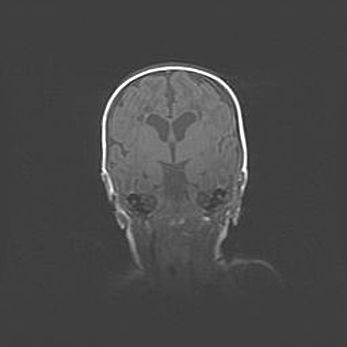

Наружная гидроцефалия с возможной атрофией височных областей.

Возраст: 28 дней

Вес: 3670 г

Пол: мужской

Окружность головы: 38 см

Срок гестации: 40 недель

Гидроцефалия головного мозга у новорожденных – это заболевание, которое характеризуется скоплением избыточного количества спинномозговой жидкости в желудочковой системе головного мозга в результате затруднения её перемещения от места выработки к месту поглощения в кровеносную систему или вследствие нарушения абсорбции. При открытой наружной форме гидроцефалии у новорожденных расширяются и переполняются субарахноидные пространства.

При нормотензивных  формах,  которые,  как  правило,  являются  следствием  перенесенных ишемических  повреждений  паренхимы  мозга,  возможно  сочетание микроцефалии  с нормотензивной гидроцефалией. В основе данных изменений лежит атрофия больших полушарий с преимущественной  локализацией  в  лобно-височных  областях.